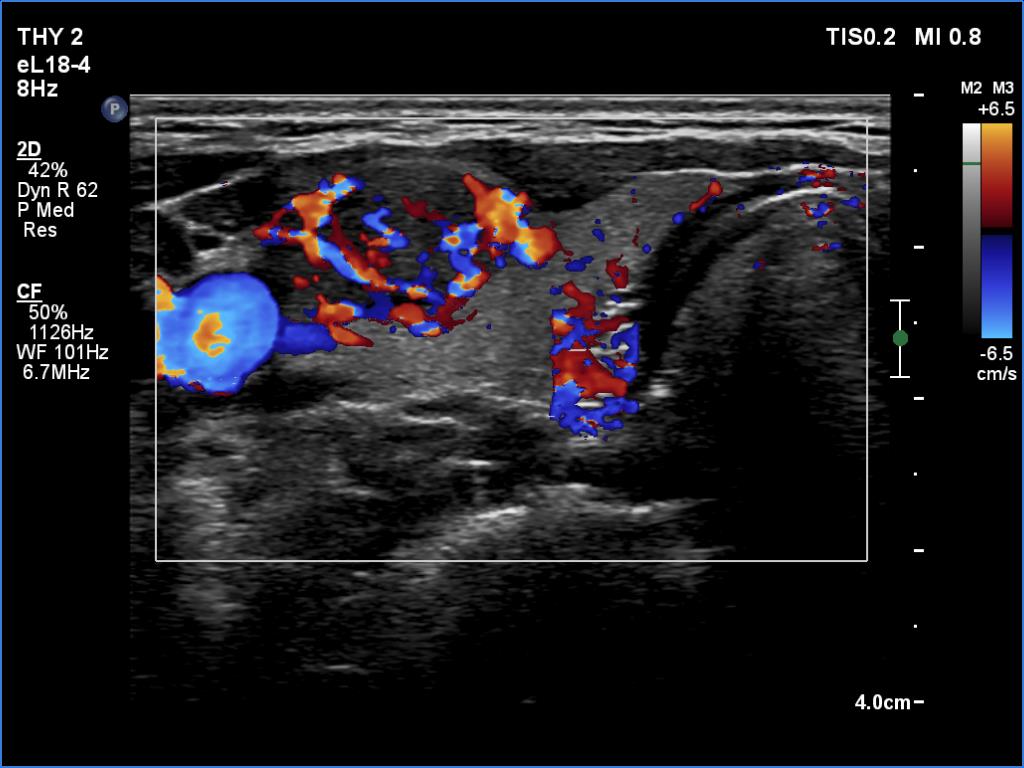

Ultrasonography. The thyroid was echonormal and presented two discrete lesions in the right lobe. The larger, upper one showed irregular margins, abutting and bulging contours and had back wall figures. The intranodular vascularization was significantly increased. The smaller lesion had microcalcifications and presented taller-than-wide shape.